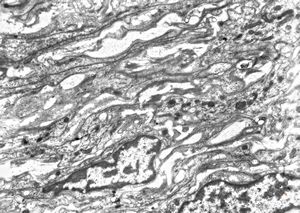

![F,23y. | n.suralis - hypertrophic demyelinating neuropathy [onion bulb] F,23y. | n.suralis - hypertrophic demyelinating neuropathy [onion bulb]](../img/OGDEM/015 Soft tissues/0076.jpg)

F,23y. | n.suralis - hypertrophic demyelinating neuropathy [onion bulb]